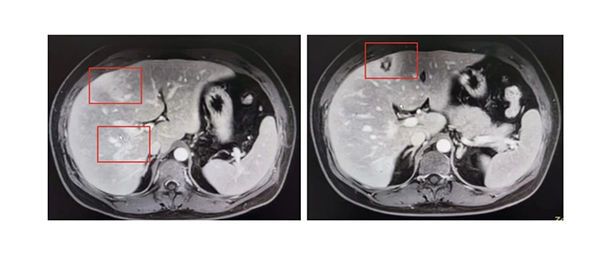

本病例于2023年8月由急诊内科接诊,38岁男性,主因“间断反复发热10余天,突发腹痛1小时”来诊,既往体健。近日因反复发热,就诊于多家医院,根据实验室检验及影像学检查结果,初步诊断为“肝脓肿”,经过积极的抗感染治疗10天,患者仍间断发热,右上腹疼痛、乏力、食欲减退等症状加重,复查CT见肝内低回声区较前明显增多,且伴嗜酸性粒细胞异常升高(正常嗜酸性粒细胞百分比为0.4%-8%,患者最高达47.7%,并且对比之前血常规结果,有进行性升高趋势),这一结果引起急诊医生的高度警惕。不明原因发热伴嗜酸性粒细胞升高,在排除肿瘤、血液系统、自身免疫等相关可能疾病后,高度怀疑是否存在寄生虫感染,再追问病史,该患发病前1月余有进食生鱼片史。由此,外院送检寄生虫相关检查,结果回报:肝吸虫IgG抗体阳性,粪便液基寄生虫检测可见肝吸虫虫卵。最终诊断:肝吸虫病。患者经积极正规的3个疗程治疗,最终治愈。值得庆幸的是,与患者同时食用生鱼片的家人在无症状的情况下进行寄生虫抗体、粪便及腹部增强核磁等相关检查,均确诊“肝吸虫病”,家属得到早期有效治疗,避免不良预后的发生。